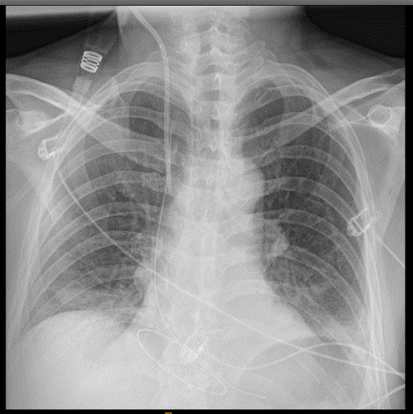

Hombre de 63 años sin antecedentes personales relevantes que consulta por dolor costal en relación con accidente de moto a baja velocidad (20 km/h). Exploración física: Valorado en el servicio de urgencias hospitalario con dolor a punta de dedo en parrilla costal izquierda a nivel de 8º-9º arcos costales anteriores izquierdos, sin deformidad ni volet costal. Hemodinámicamente estable a su llegada con saturación basal de O2 al 98%. Auscultación cardiopulmonar normal y abdomen sin defensa ni signos de irritación peritoneal. Pruebas complementarias: Dado el mecanismo lesional se solicita radiografía de tórax donde se objetivan fracturas costales no desplazadas de 8º-9º-10º arcos costales izquierdos. Se solicita análisis de sangre y se deja en observación para control del dolor.